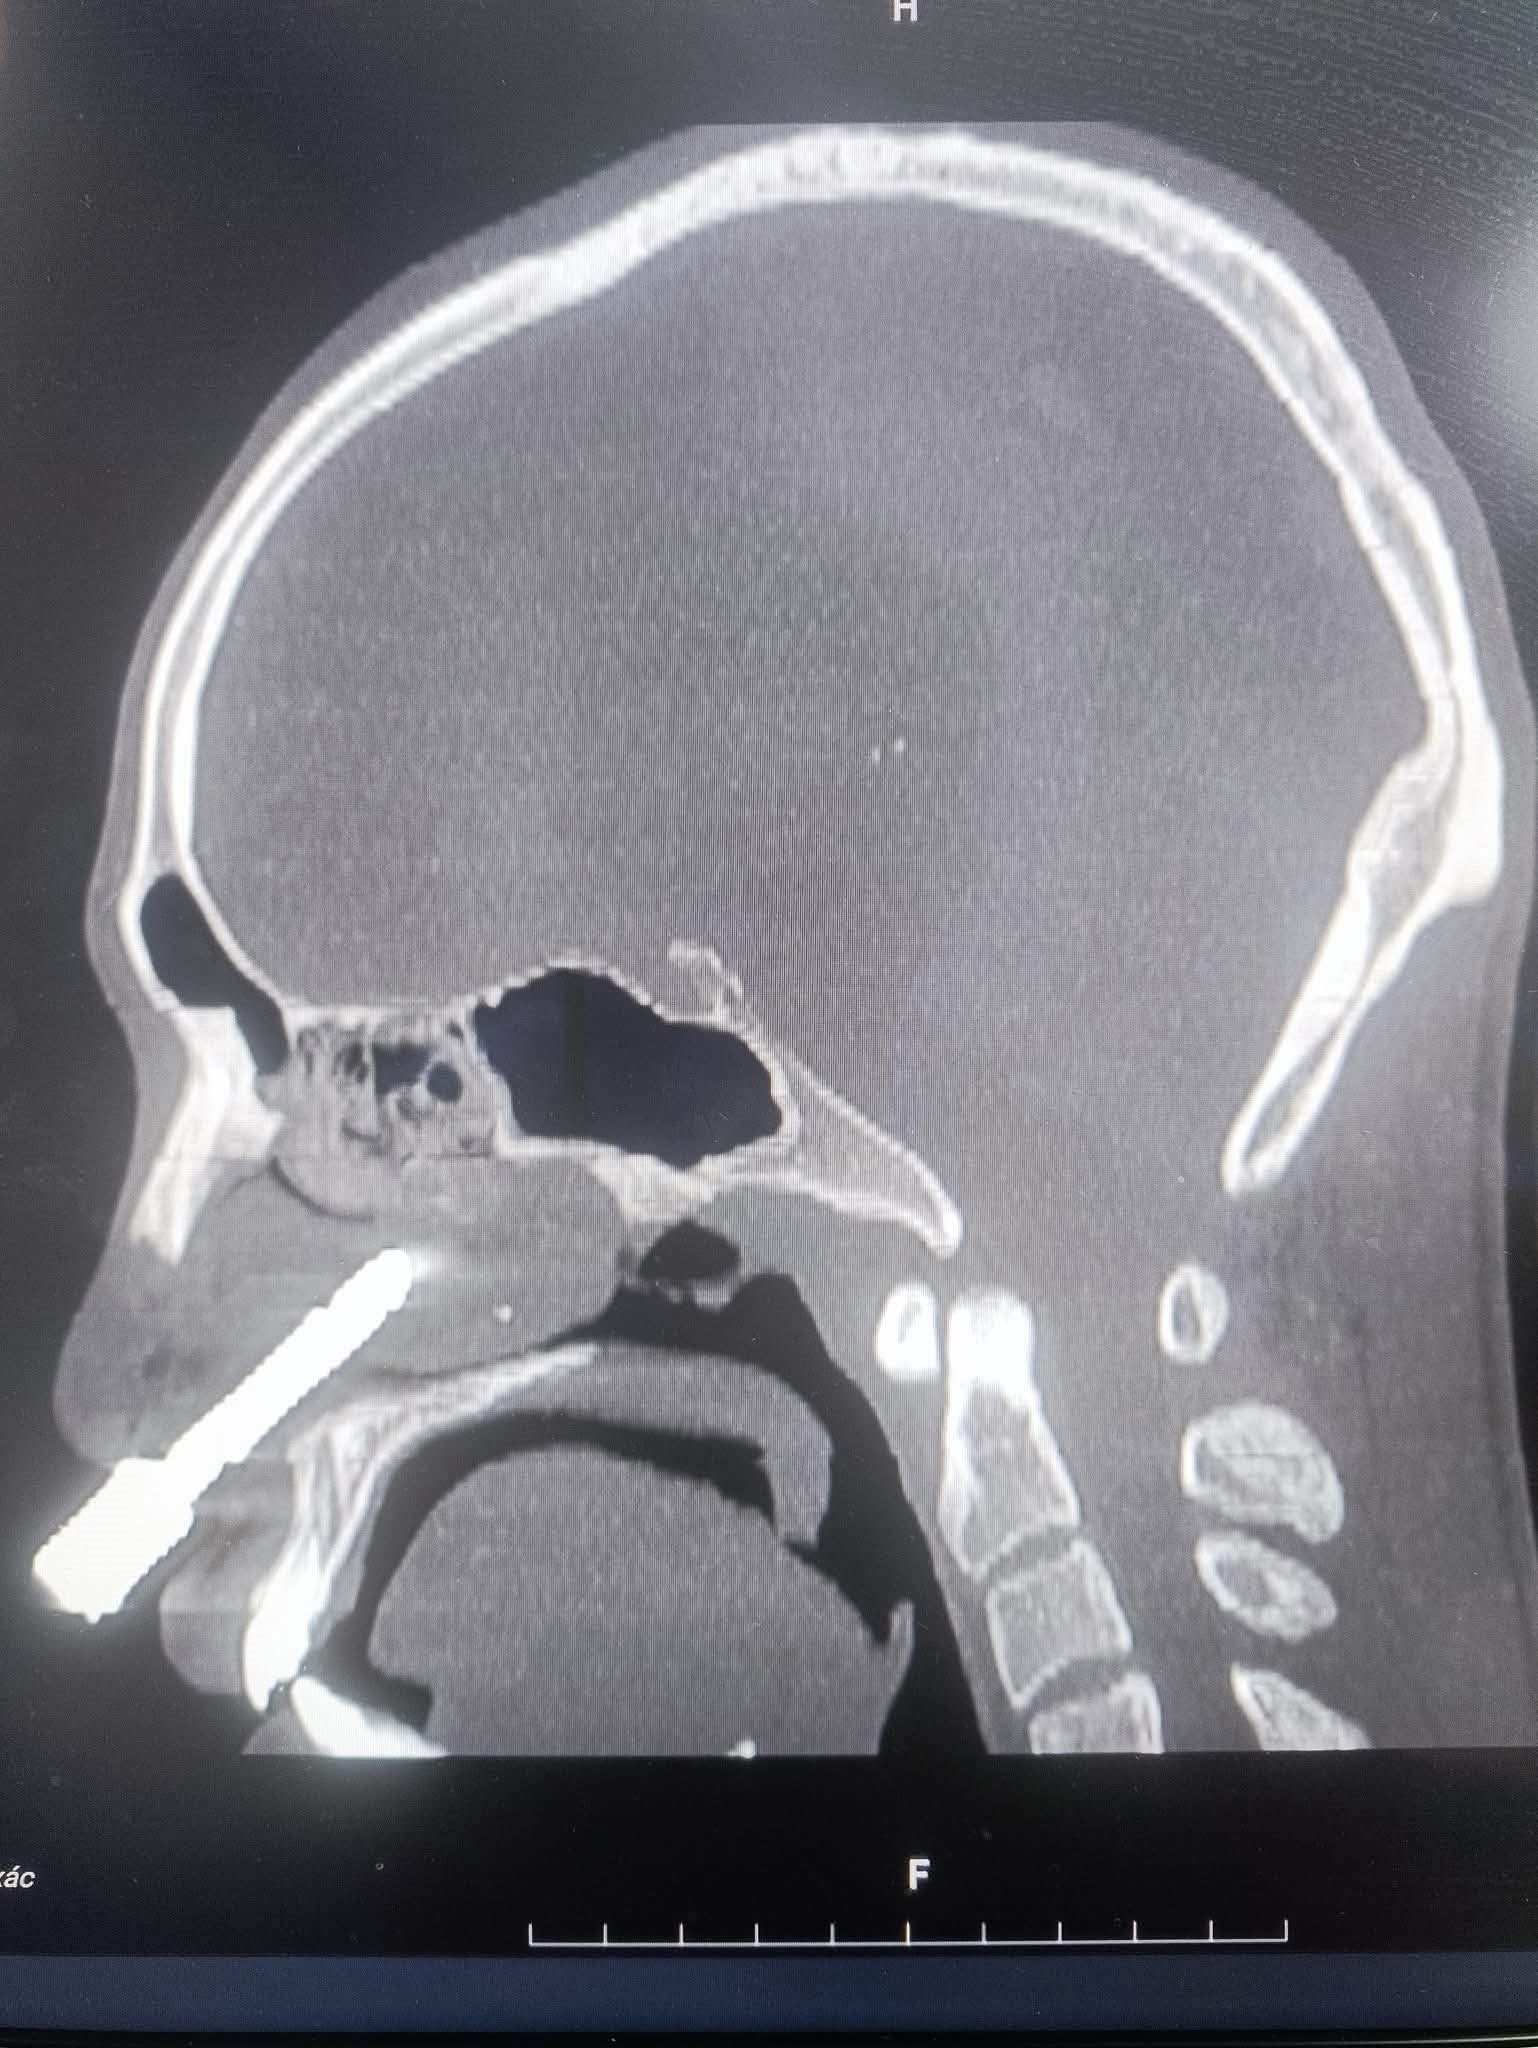

Hình ảnh mũi khoan cắm sâu vào hốc mũi nam bệnh nhân |

Kết quả chụp cắt lớp vi tính (CT-Scan) và dựng hình ảnh 3D cho thấy dị vật là một mũi khoan kim loại dài khoảng 7–8cm, có hình cong như lưỡi câu, đâm từ hốc mũi phải xuyên thủng hoàn toàn vách ngăn mũi, đầu móc cong cắm sâu vào hốc mũi trái. Khiến phần cuống mũi dưới bị rách nặng, toàn bộ vách ngăn bị thủng lớn. Bệnh nhân được chỉ định phẫu thuật cấp cứu ngay lập tức.